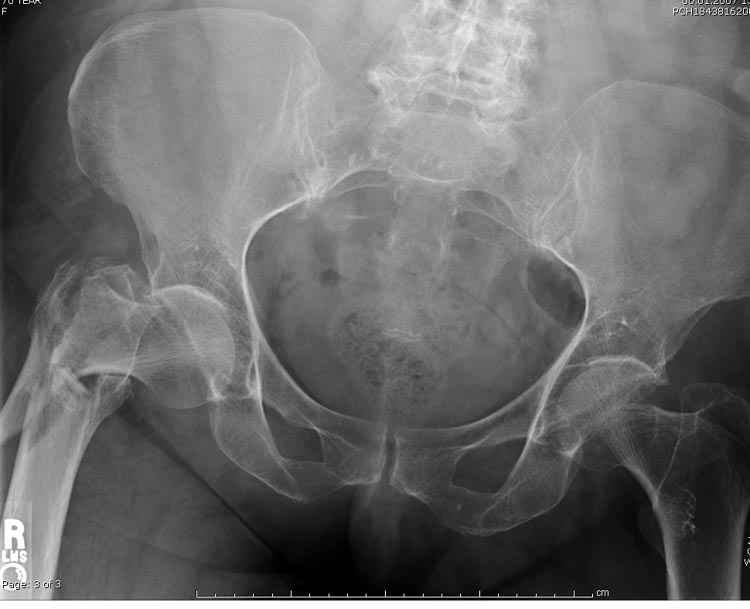

Re: оскольчатый чрезвертельный перелом

А что тут заставляет сомневаться? Здесь настолько очевидно предпочтителен закрытый интрамедуллярный остеосинтез реконструкционным стержнем (проксимальные гвозди толстоваты для такого молодого возраста), что закрадывается мысь о каком-то подвохе.

Желательно бы и снимок бедра на протяжении и в другой проекции.

Не солидно экономить на пленке, это не делает чести презентации. Такие ограниченные нестандартные снимки приводят к тактическим ошибкам.

Предугадать распространение линий перелома при чрезвертельных и оскольчатых переломах трудно, поэтому для принятия правильного решения рекомендуется Компьютерно Томографические исследование.

При отсутствии КТ, снимок на вытяжении поможет увидеть общую картину расположения отломков, особенно потенциальные места введения импланта. Риск раскола в этом случае огромный, поэтому больной должен быть дообследован.

А так для лечения оскольчатых переломов подходят все методы, включая интра- и экстрамедуллярные в зависимости от опыта и наличия импланта.